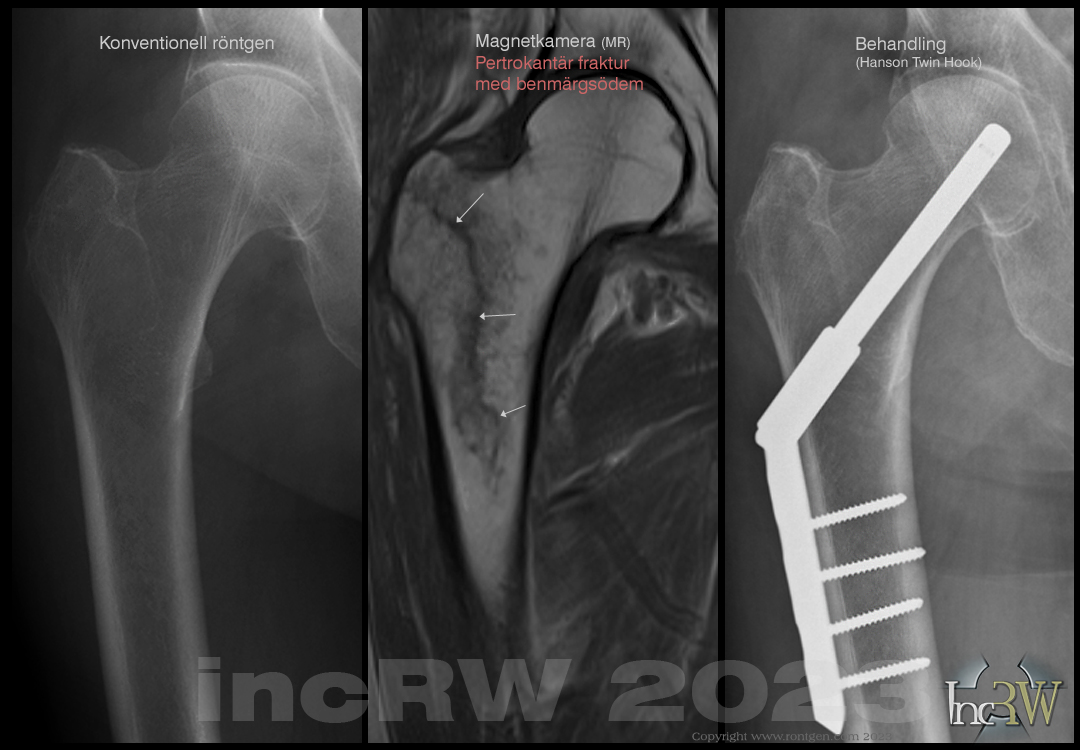

Det såg relativt bra ut. Det jag undrar över är vad det betyder när det står. På höger sida nedom och framför trochanter minor finns ett relativt diskret subcorticalt benmärgsödem av tveksam klinisk signifikans sitter ej på vanligt ställe för stressreaktion.

Ett benmärgsödem är en skada i benmärgen vilket kan ses vid en skada i höften trots att benhinnan (periostet) inte brutits igenom. Denna ”skada” kan uppstå vid trauma (slag/våld) mot exv. höften. Man kan likna det vid ett blåmärke innuti benet vilket uppstår då små blodkärl i benmärgen gått sönder. Även infektion och nekroser i benet kan ses som märgödem på MR-bilderna. Exv. märgödem kring ländrygg/bäckenleden (sakroiliakaleden) kan ibland tyda på kronisk inflammatorisk process (t.ex. Bechterew).

Ett benmärgsödem kan ses som ett symtom på patologi och inte en klar diagnos. Det kan behövas följas upp om man inte har en direkt påvisbar orsak till benmärgsödemet.

Vad gäller höftbensödem kan detta skilja mellan en genomgående fraktur som inte ses med konventionell röntgen eller en mindre avlossning av ett ligamentfäste, etc. som inte behöver åtgärdas